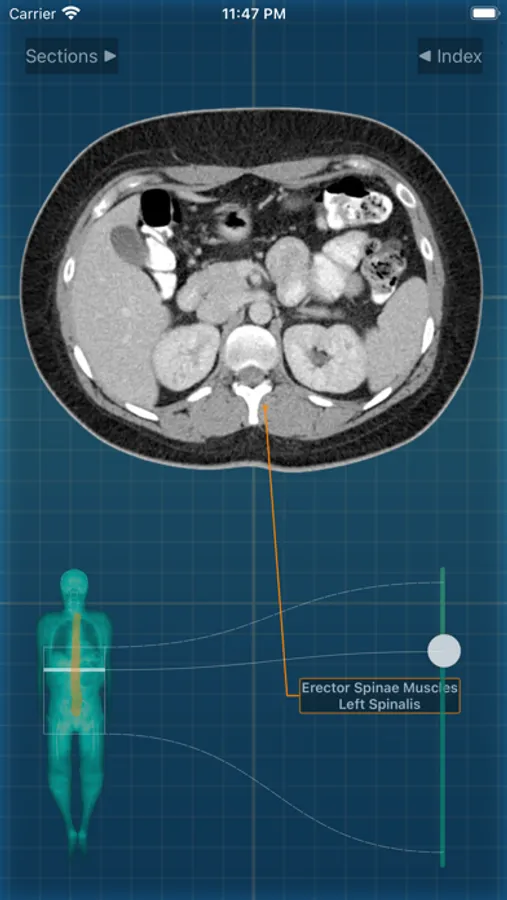

X-Anatomy is a transaxial cross-sectional human anatomy interactive medical imaging atlas using CT images, designed for medical professionals & all students of anatomy.

* FOLLOW the positions and pathways of your selected anatomic structures automatically as you SCROLL through the image slices.

* Use the intuitive BODY LOCALIZER to show you where you are as you scroll through the body, as well as the general region of the anatomic structure

INCLUDED body section modules cover the major body sections from head to pelvis: CT Brain, CT Neck, CT Sinuses, CT Chest, CT Lungs, CT Abdomen & Male Pelvis, CT Abdomen & Female Pelvis.